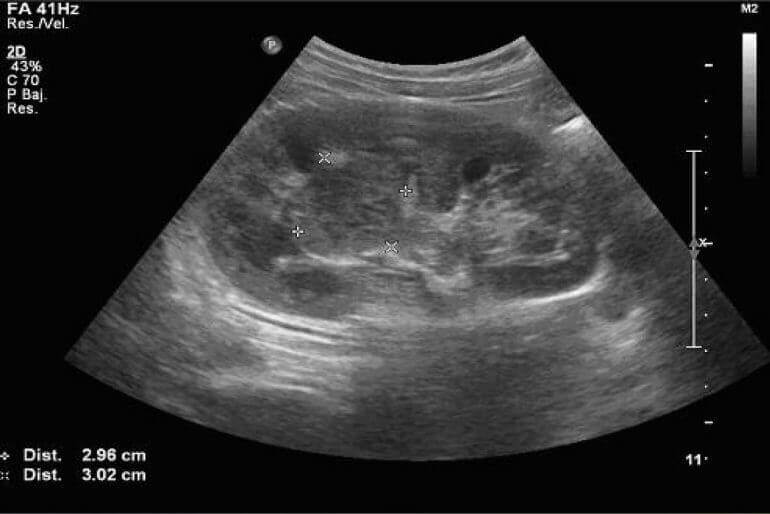

En la mayoría de los casos, durante este período el bebé cuenta con un grado de desarrollo en sus órganos y huesos. Debido a esto el Ultrasonido Morfologico se realiza con el fin de asegurar el buen funcionamiento de estos, incluyendo las extremidades y la cabeza. Durante el ultrasonido Morfologico también se evalúa la biometría, donde se miden de igual forma los órganos y extremidades para comprobar que existe un desarrollo correcto

Revisamos detalladamente las medidas de tu pequeño en base a las medidas promedio con el fin de saber si su ritmo de crecimiento es normal. Entre las medidas que realizamos se encuentran la del pliegue nucal, la anchura de la cabeza, el abdomen, el cerebelo, entre otros.